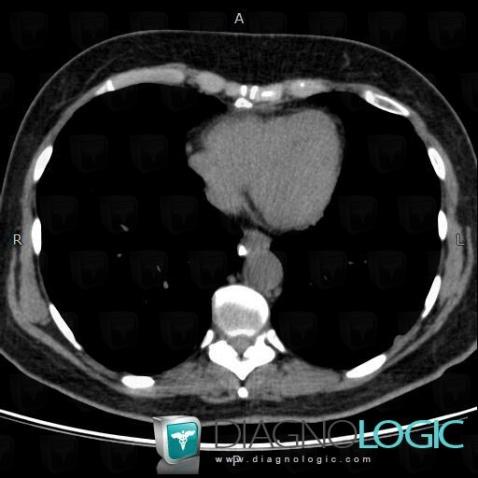

Les images ci-dessous illustrent ce dossier pour les diagnostics Sarcoïdose (lié à Fibrose pulmonaire), Sarcoïdose, pour les modalités (Scanner)

Voici les informations spécifiques à l'image clé ci dessus:

- Diagnostic Sarcoïdose, Localisation(s) Médiastin, comportant les gammes Adénomégalie hilaire